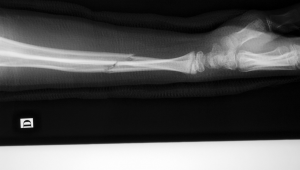

胳膊骨折后能否踢足球,这是众多骨折患者及足球爱好者极为关心的问题。胳膊骨折意味着身体的一部分受到了损伤,而足球运动对身体的协调性、力量和灵活性都有着较高要求。当胳膊骨折时,身体的原有平衡和运动能力会被打破。从骨折后的身体恢复角度来看,胳膊骨折需要经历一系列的愈合阶段。初期,骨折部位需要妥善固定,以促进断端的初步连接和稳定,这个阶段身体的活动会受到很大限制,别说踢足球,就连基本的日常活动都需要小心翼翼。随着时间推移,骨折部位逐渐开始愈合,会经历纤维性骨痂形成、骨性骨痂形成以及骨痂改建塑形等过程。在整个恢复过程中,身体的机能需要逐步调整和适应,尤其是受伤胳膊所在一侧的身体协调性和力量运用。

胳膊骨折后短期内是绝对不可以踢足球的。骨折刚发生时,断端不稳定,剧烈运动很可能导致骨折断端移位,进而加重损伤,影响愈合进程。移位后的骨折可能会刺破周围的血管、神经,引发更严重的并发症,比如出血不止、肢体麻木、感觉异常等。在骨折固定期,受伤的胳膊无法正常发挥其在足球运动中的作用,像传球、接球、射门等动作都需要双臂的配合。而此时胳膊被固定,强行参与足球运动不仅会给受伤部位带来极大痛苦,还可能因为身体其他部位过度代偿而引发新的损伤。比如,可能会导致肩部、腰部等部位承受额外的压力,长期下来容易造成这些部位的劳损或损伤。

即使胳膊骨折经过一段时间初步愈合,也不能贸然去踢足球。虽然骨折部位开始有了一定的连接,但此时骨骼的强度还远未恢复到正常水平。足球运动中频繁的奔跑、激烈的对抗、大幅度的肢体动作,都可能对尚未完全愈合的胳膊造成二次伤害。例如,在与对方球员碰撞时,受伤的胳膊可能再次受到冲击,导致骨折再次断裂。而且,身体在骨折恢复过程中,肌肉力量、关节灵活性以及整体协调性都需要重新训练和恢复。如果在这些方面没有达到足球运动所要求的水平,强行参与足球,很容易在运动中出现动作变形,增加受伤的风险。